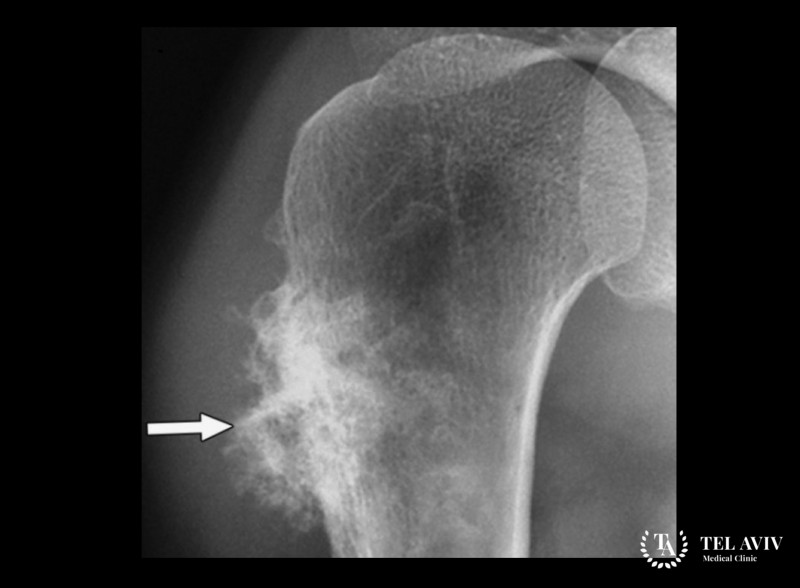

- Рентгенологическое обследование.